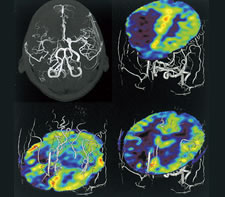

MRIは磁気と電磁波、水素原子の共鳴現象を利用して、体の断面の画像を得ることができる撮影方法です。機器が発する磁界が強いほど鮮明な画像を得ることができます。軟部組織のコントラストに優れ、様々なコントラストパラメーターを有するMRIは、頭頚部、体幹部、脊椎・脊髄、整形領域、心臓領域とほぼ全身に渡る断層画像をあらゆる角度で撮像できます。さらに検査にX線は使用しませんので、放射線被曝の心配がありません。

造影剤を用いることなく非侵襲的な脳灌流の撮像が可能です。脳底部でも歪みのない画像を取得できます。